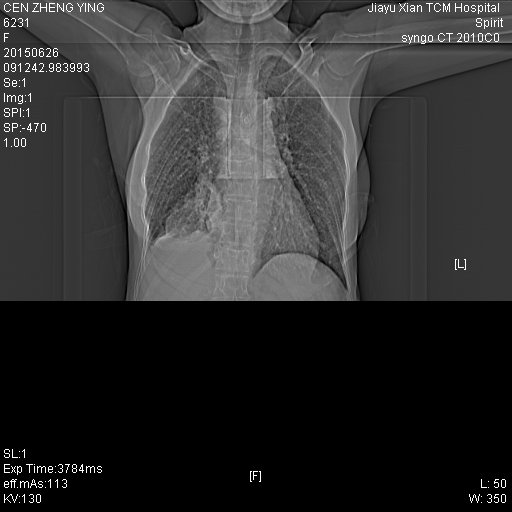

CT50742:女.65岁.胸部不适

右下肺周围性肺癌伴两肺门纵隔淋巴结转移,两侧胸腔少量积液。

右下肺中央型肺癌,两肺、心包及纵隔淋巴结转移

肺下叶周围型肺癌并右肺门及纵隔淋巴结转移,两肺弥漫性转移

考虑右肺癌伴双肺、纵隔淋巴结转移。

考虑中央型肺Ca并肺门纵膈淋巴结转移,还是做个增强吧。

右肺下叶中央型肺癌并阻塞性肺不张,伴两肺及纵膈淋巴结转移。

肺癌肺内转移纵隔淋巴转移,右侧胸腔积液